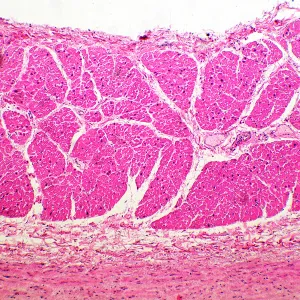

Микроскоп MAGUS Bio 260T – рутинный, с ним можно проводить лабораторные и научные исследования, или использовать его для учебного процесса. Микроскоп работает с тонкими прозрачными и полупрозрачными препаратами в светлом поле. Однако на прибор можно поставить дополнительные компоненты, которые расширят его возможности для проведения исследований по методам темного поля, фазового контраста, в поляризованном и люминесцентном свете.